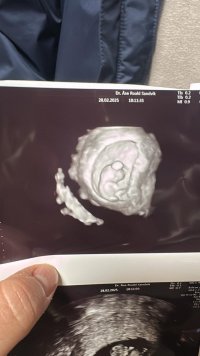

9+0, 178 bpm og 2,3cm lang. Perfekt liten miniatyrbaby som danset for oss på skjermen!